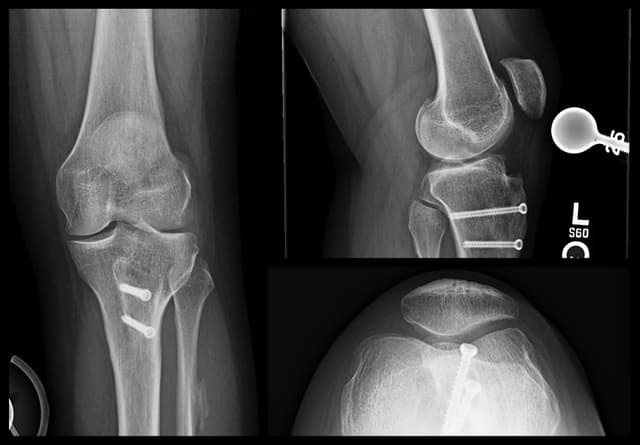

Imaging

Pre-op